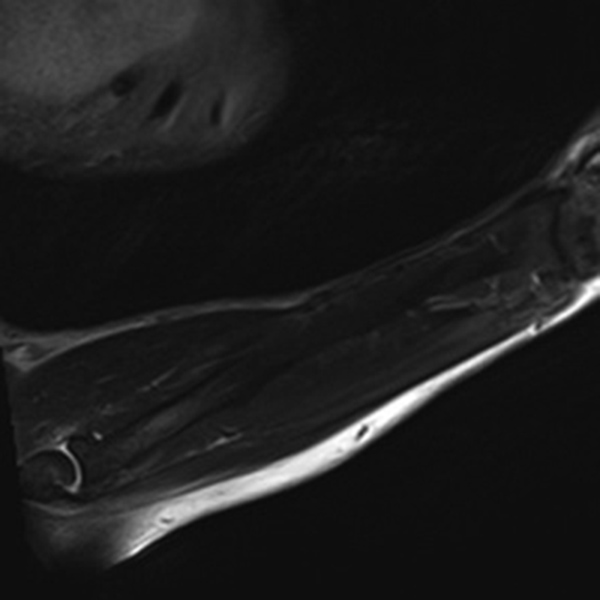

Shading Artifact. (A) Incomplete coil coverage results in dark signal obscuring the soft tissues adjacent to the olecranon at the periphery of sagittal STIR image of the forearm in a patient with cellulitis and concern for abscess. (B) Axial T1-weighted post-contrast fat-saturated image obtained following coil repositioning demonstrates abscess (arrow) in the previously obscured region.